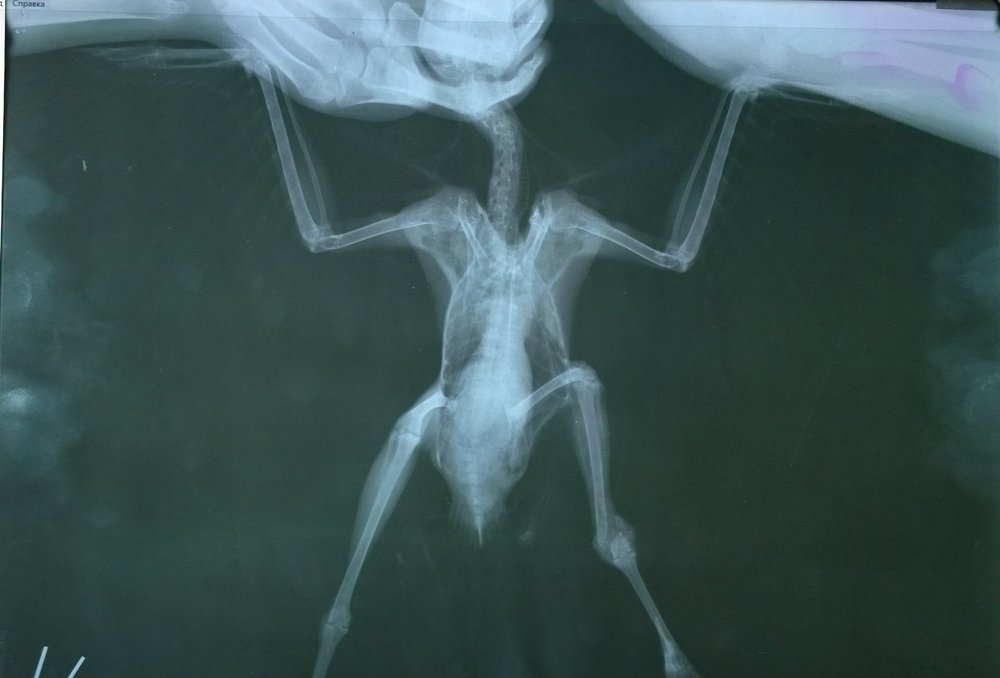

Доброго времени суток! позавчера вечером подобрала грача.Изначально. проблема с лапой. Только сегодня удалось сделать рентген. Отправили в другую клинику. Записаны на субботу на консультацию к хирургу по снимкам.Подскажите, пожалуйста, насколько все печально, исходя их снимков, что нужно делать и не нужно. и на сколько целесообразен в данном случае остеосинтез. Заранее спасибо